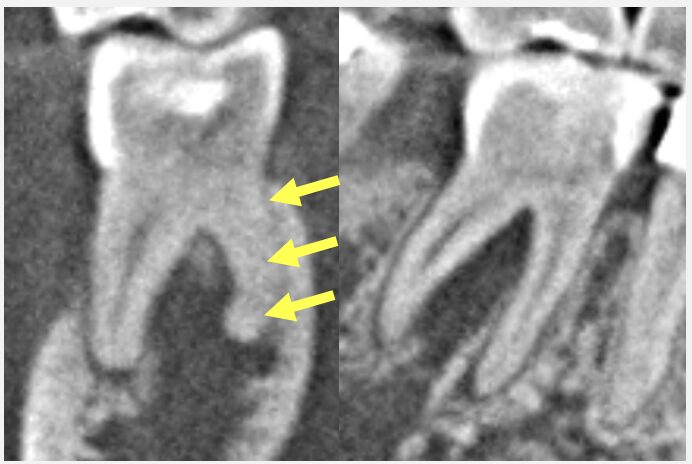

こちらの資料をご覧ください。これは、歯の中の神経の状態を、ステージ1から4にわけたものです。歯をぶつけて神経が死んでしまうことを、歯髄壊死といいます。これは歯の神経の状態としては末期で、残念ながら元の状態に戻ることはありません。

放置すると、歯が変色してくるだけでなく、根の先の骨を溶かす問題にもつながります。そのため、根管治療が第一選択となります。